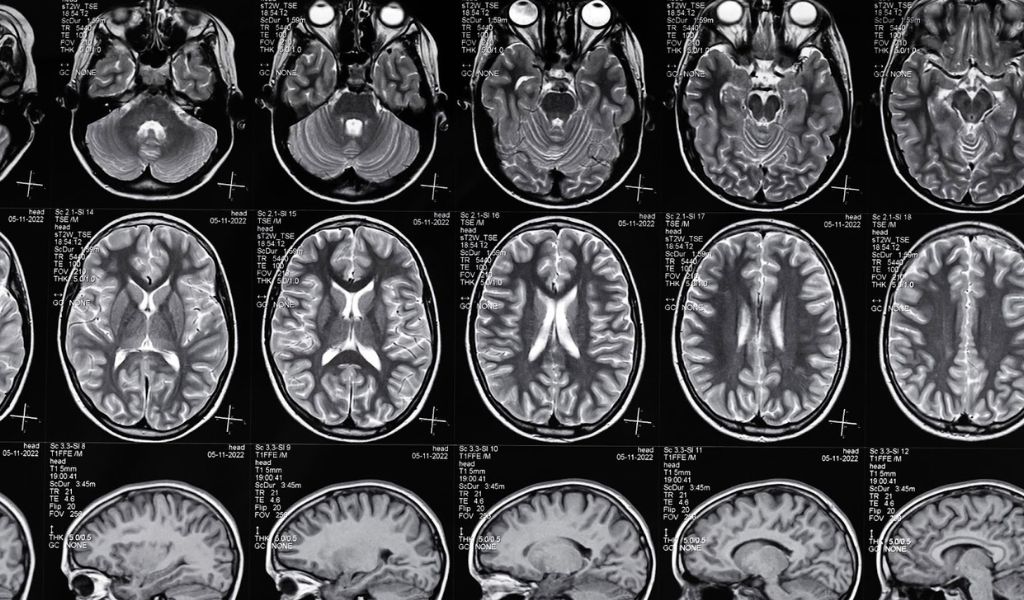

However, six months later, the symptoms worsened. An MRI finally flagged subtle, long-term damage that wasn’t visible on the surface.